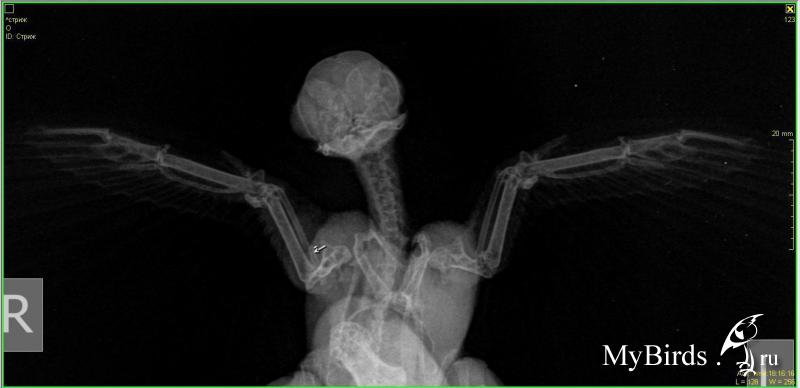

lilamor Опубликовано 25 июля, 2017 #1 Опубликовано 25 июля, 2017 Здравствуйте! Хочу спросить про этого стрижа. Он живет у моей знакомой. Привезли с переломом. Первый снимок (две фотографии) 30 мая, второй (тоже две) - 29 июня. Из лекарств она давала B1 и мелоксикам. Говорит, не может набрать высоту. Кормит сверчками и тараканами, чистит их как положено и тренирует его. "По распорядку - кормлю утром в 8:00 (примерно, бывает на выходных позже), вечером в 18:00ночью в 00:00 Тренировки - каждый день по буднях 1 раз вечером пускаю на накрытое покрывало, на выходных раза 3 в день.Перестал крылохлопить, когда сообразил, что внизу пол, а для него пол - это свобода))или висит на покрывале и не шелохнется. Если беру в ладошку- он слетает на покрывало, это единственный вариант тренировки для него, по-другому не получается. я его просто беру над ковром и над покрытым покрывалом слева (то есть покрывало закреплено на чем-то высоком у стены, спинки дивана, а к другой стороне оно опущено под углом). и держу - он начинает активничать и летит вниз на мягкое. Беру его всегда в перчатках! Хотя сначала не делала этого, о чем жалею( запылились немного перья, я периодически хлоргексидином прохожусь ватным диском."Вот тут видео как он летает https://vk.com/im?sel=26594438&z=video2...6a542ae99c5e316. Вопрос по снимкам: лучше или хуже стало? Что еще можно сделать? Есть надежда на полёт? Или он навсегда останется домашним питомцем?

Anysya Опубликовано 25 июля, 2017 #2 Опубликовано 25 июля, 2017 небольшая надежда у птицы была. так как смещение незначительное, хотя и перелом в очень плохом месте. т.е. результат был бы гадательным.шанс на успех был при условие полного покоя на полтора месяца. никакого обезбаливания - только боль заставляет сидеть спокойно первые две недели и кость встает на место, срастается идеально. мелоксикам в таком случае снижает шанс на подобный исход практически на 100%. а заставлять птицу тренироваться и летать с уже нарушенным сращиванием и недостаточной костной мозолью - именно для этого следующий месяц после первых двух недель - это просто издевательство. тем более, стриж и не нуждается в подобных тренировках и сам способен решить когда и как ему тренироваться.в общем, шансов на вылет практически не осталось. птицу жаль.